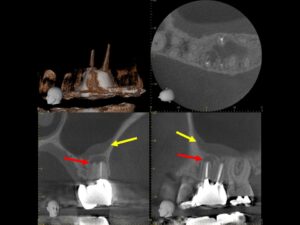

初診時CT。根管治療を何度も繰り返し行ったことで、歯根は無駄に削られて歯質が薄くなり、歯根の先端には穿孔(パーフォレーション)を生じていた。根尖病巣は認めない。